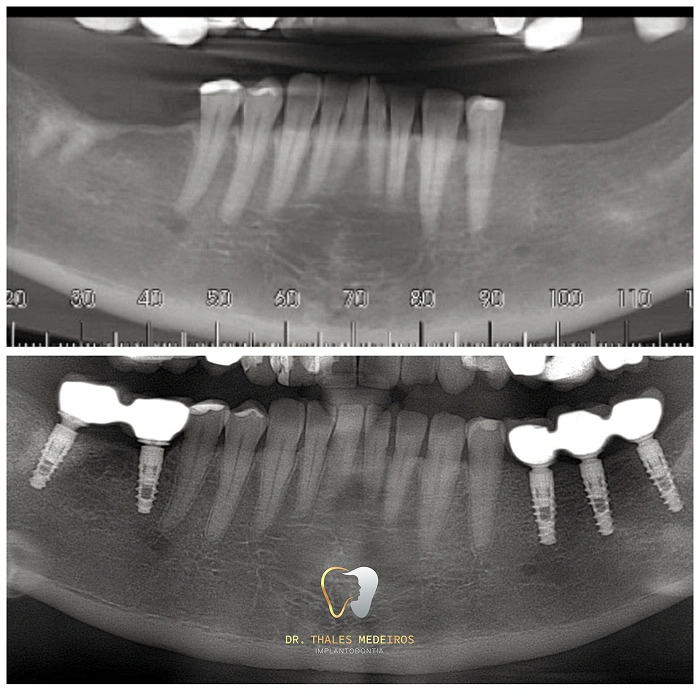

Implantes Dentários: Sorrisos restaurados com segurança e precisão

Recupere seu sorriso e sua qualidade de vida com os implantes dentários do Dr. Thales Medeiros. Com 9 anos de experiência e quase 2.000 implantes realizados, ele é referência na Paraíba em reabilitação oral. Os implantes proporcionam benefícios como restauração da mastigação, preservação da estrutura óssea, estabilidade dentária duradoura, melhora da estética do sorriso e aumento da autoestima.

Cada procedimento é planejado de forma personalizada, unindo tecnologia de ponta e cuidado humanizado para oferecer resultados seguros e naturais.

Já são quase 2.000 implantes realizados: segurança, conforto e resultados naturais para seu sorriso.